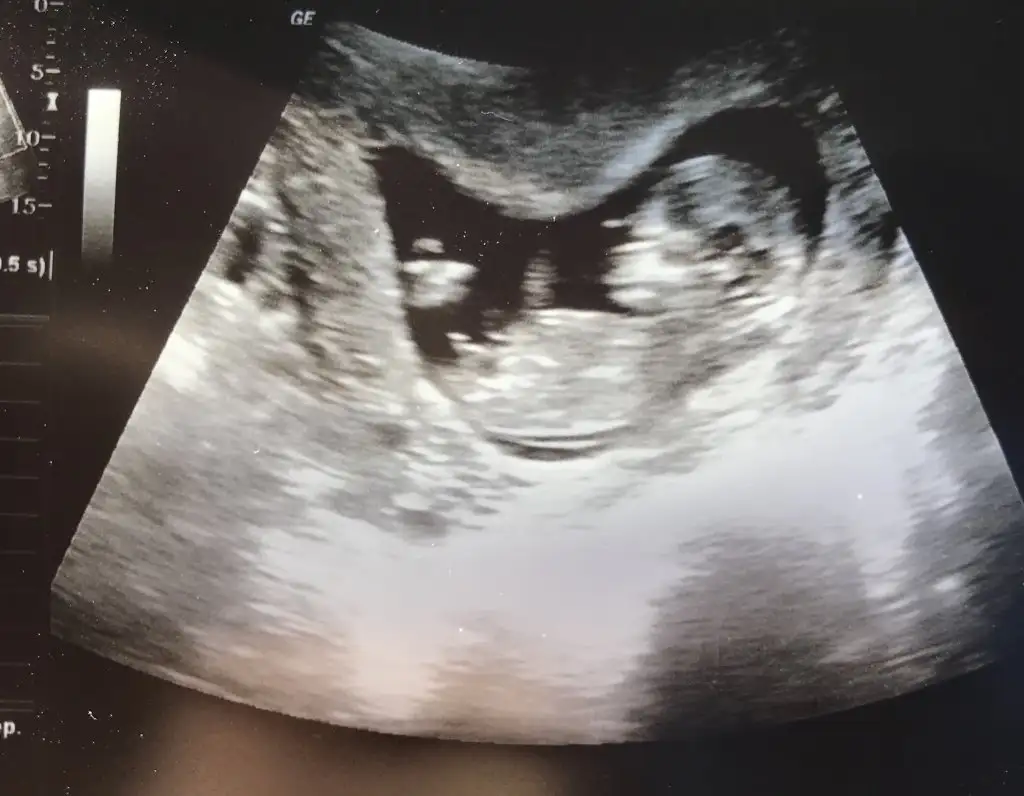

ErkekEki Görüntüle 2562668 Kızlar tahminleri alayım

Maasallah sanki bıldıgın erkek pek anlamamda hakikaten cıkıntı varEki Görüntüle 2562668 Kızlar tahminleri alayım

Bence erkekEki Görüntüle 2562668 Kızlar tahminleri alayım